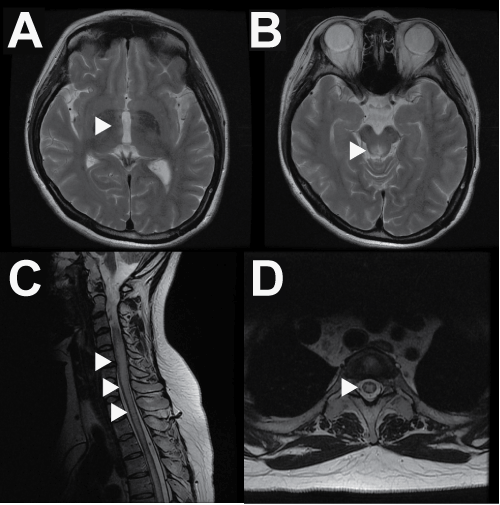

| Figure 1: Typical MRIs of SLE with NMO. (A) T2-weighted axial images indicatehyperintense lesions in the hypothalamus (B) and periaqueductal, which highly express the aquaporin 4 molecule. (C) A T2-weighted sagittal image of the spinal cord indicates the swelling and alongitudinal lesion. (D) A T2-weighted axial image of the spinal cord indicates a hyperintense lesion in the central parts of the spinal cord. |